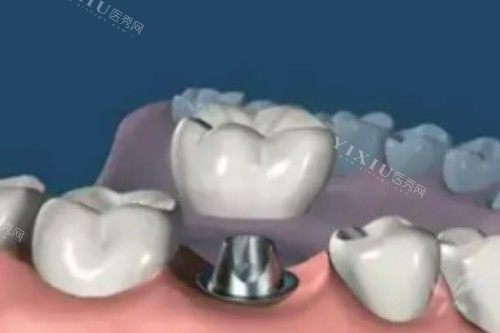

种植牙系列

韩国迪耀种植体:2878-5980元/颗(高性价比首要选择)

韩国登腾种植体:2890-12800元/颗(临床使用率高)

韩国奥齿泰种植体:8000元起/颗

美国进口种植体:9000元起/颗

瑞典诺贝尔PMC种植体:5577-15800元/颗(骨条件适配型)

瑞典诺贝尔种植体:15000-22000元/颗(高端稳定型)